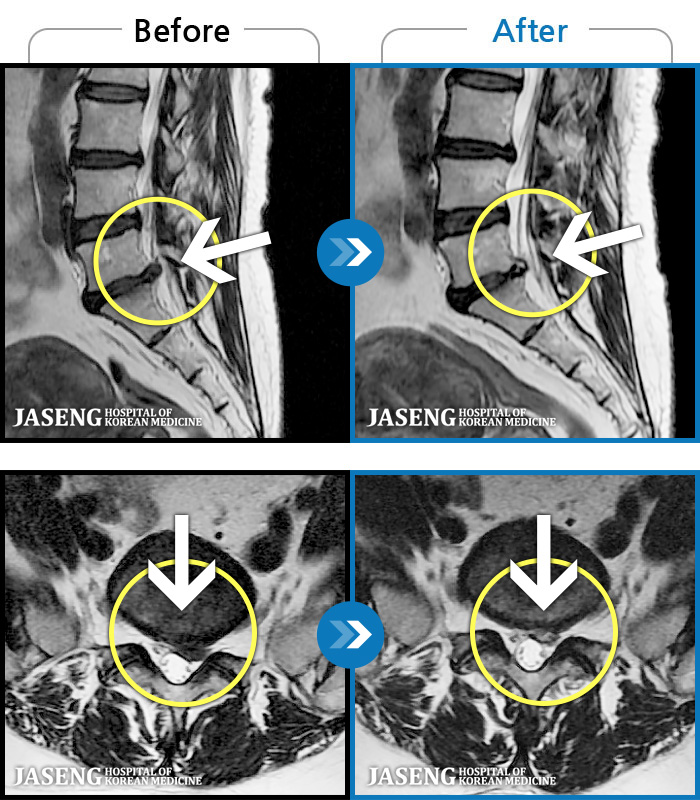

[Կñ:25.03.04~25.09.10]

[õ_㸮ũ] ߲ 㸮 , ٷ

No.1235

ȸ 139

2025.09.22